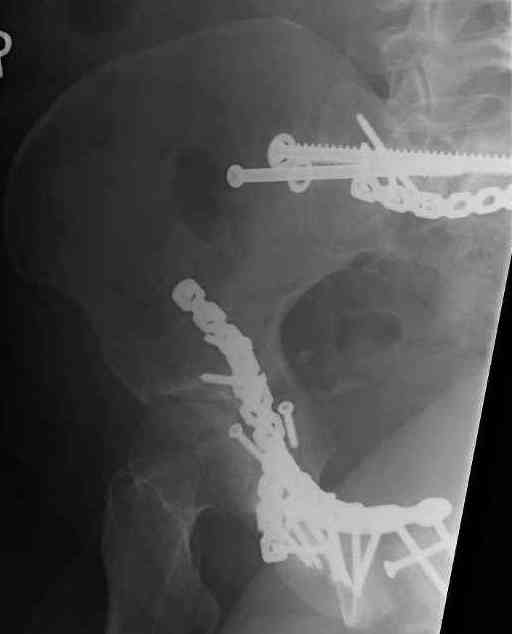

Looking for advice. This is a 48 yo non-smoking female s/p MCC 10 months ago. I do not have the initial injury films. She underwent ORIF as shown on attached file. She is having continued pain in low back/sacral region. Worse with sitting and prolonged walking. Has had pain since surgery. All of her wounds have healed uneventfully. Also has right hip pain laterally. No groin pain. Not aggravated with ROM of the hip. Infection work-up has been negative.

Any thoughts on the broken plate on the pelvic brim and the non-union on the anterior column. Doesn't seem like she's have pain from there.

Suggestions on treatment of sacral nonunion.